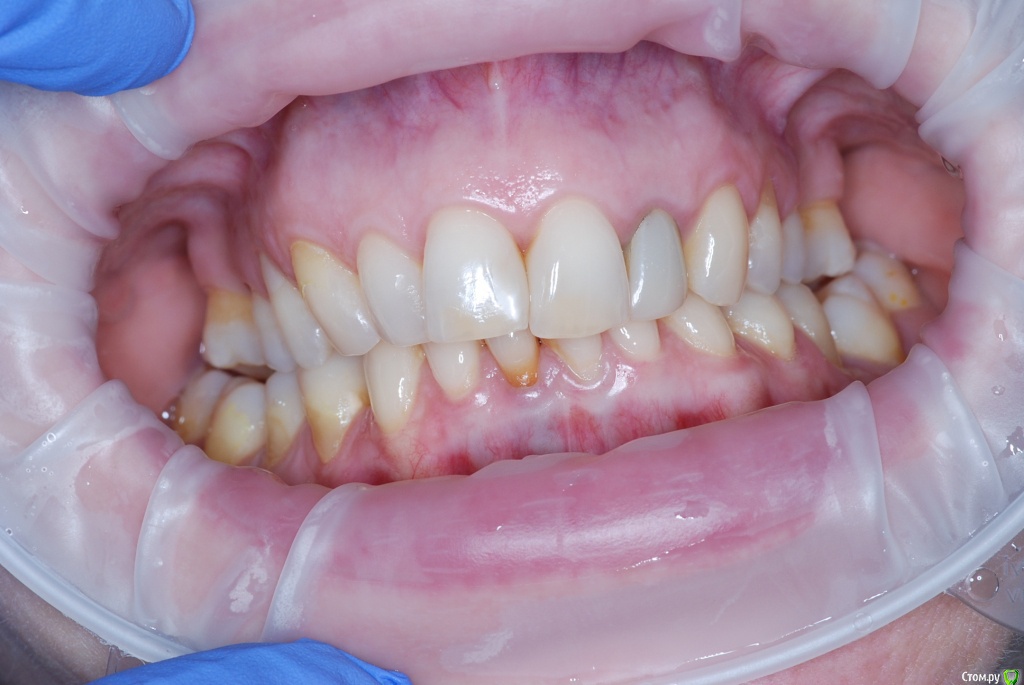

VVQW Опубликовано 6 декабря, 2016 Поделиться Опубликовано 6 декабря, 2016 В результате некачественной ортодонтии более 10 лет назад имеется такая картина. Посоветуйте что-можно сделать?Верхние 6-ки удалены перед брекет системой, по решению ортодонта. Верхние 8-ки не выросли, нижние 6-ки - удалены в подростковом возрасте до 14 лет. http://s019.radikal.ru/i639/1612/56/1345f17db908.jpg http://s019.radikal.ru/i630/1612/55/145ef7c813b2.jpg http://s017.radikal.ru/i440/1612/c2/74bd4da2643e.jpg http://s008.radikal.ru/i303/1612/b4/e80683ed7d2b.jpg http://s010.radikal.ru/i314/1612/74/6d2f9671b0d5.jpg http://s018.radikal.ru/i502/1612/97/9a15fcf4ddd3.jpg http://s020.radikal.ru/i715/1612/59/9bb4a006621f.jpg Ссылка на комментарий

VVQW Опубликовано 6 декабря, 2016 Автор Поделиться Опубликовано 6 декабря, 2016 Добрый день. Беспокоят клиновидки и их прогрессирование из-за неправильной окклюзии.Которая из-за неккоректно проведенного ортодонтическлго лечения. Одно из мнений ортодонтов, 50/50, что надо провести повторное лечение и восстановить зубной ряд имплантами. Вот только дальше варианты у всех свои. Если в верху подвинуть 7 к 5, есть место для импланта? Кость позволит? И наоборот если сделать место под 6, можно ли туда импоант поставить? Спасибо. Ссылка на комментарий